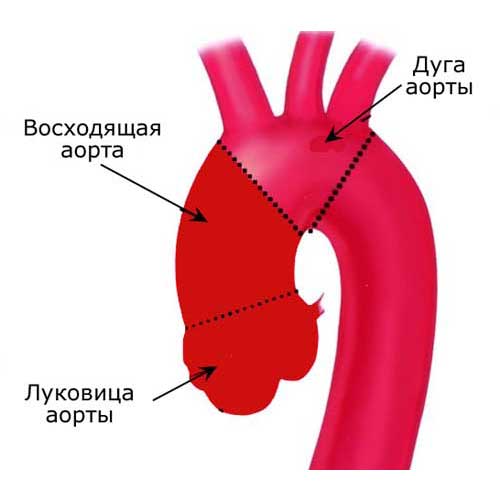

Нормальный диаметр корня аорты: медицинские нормы и отклонения